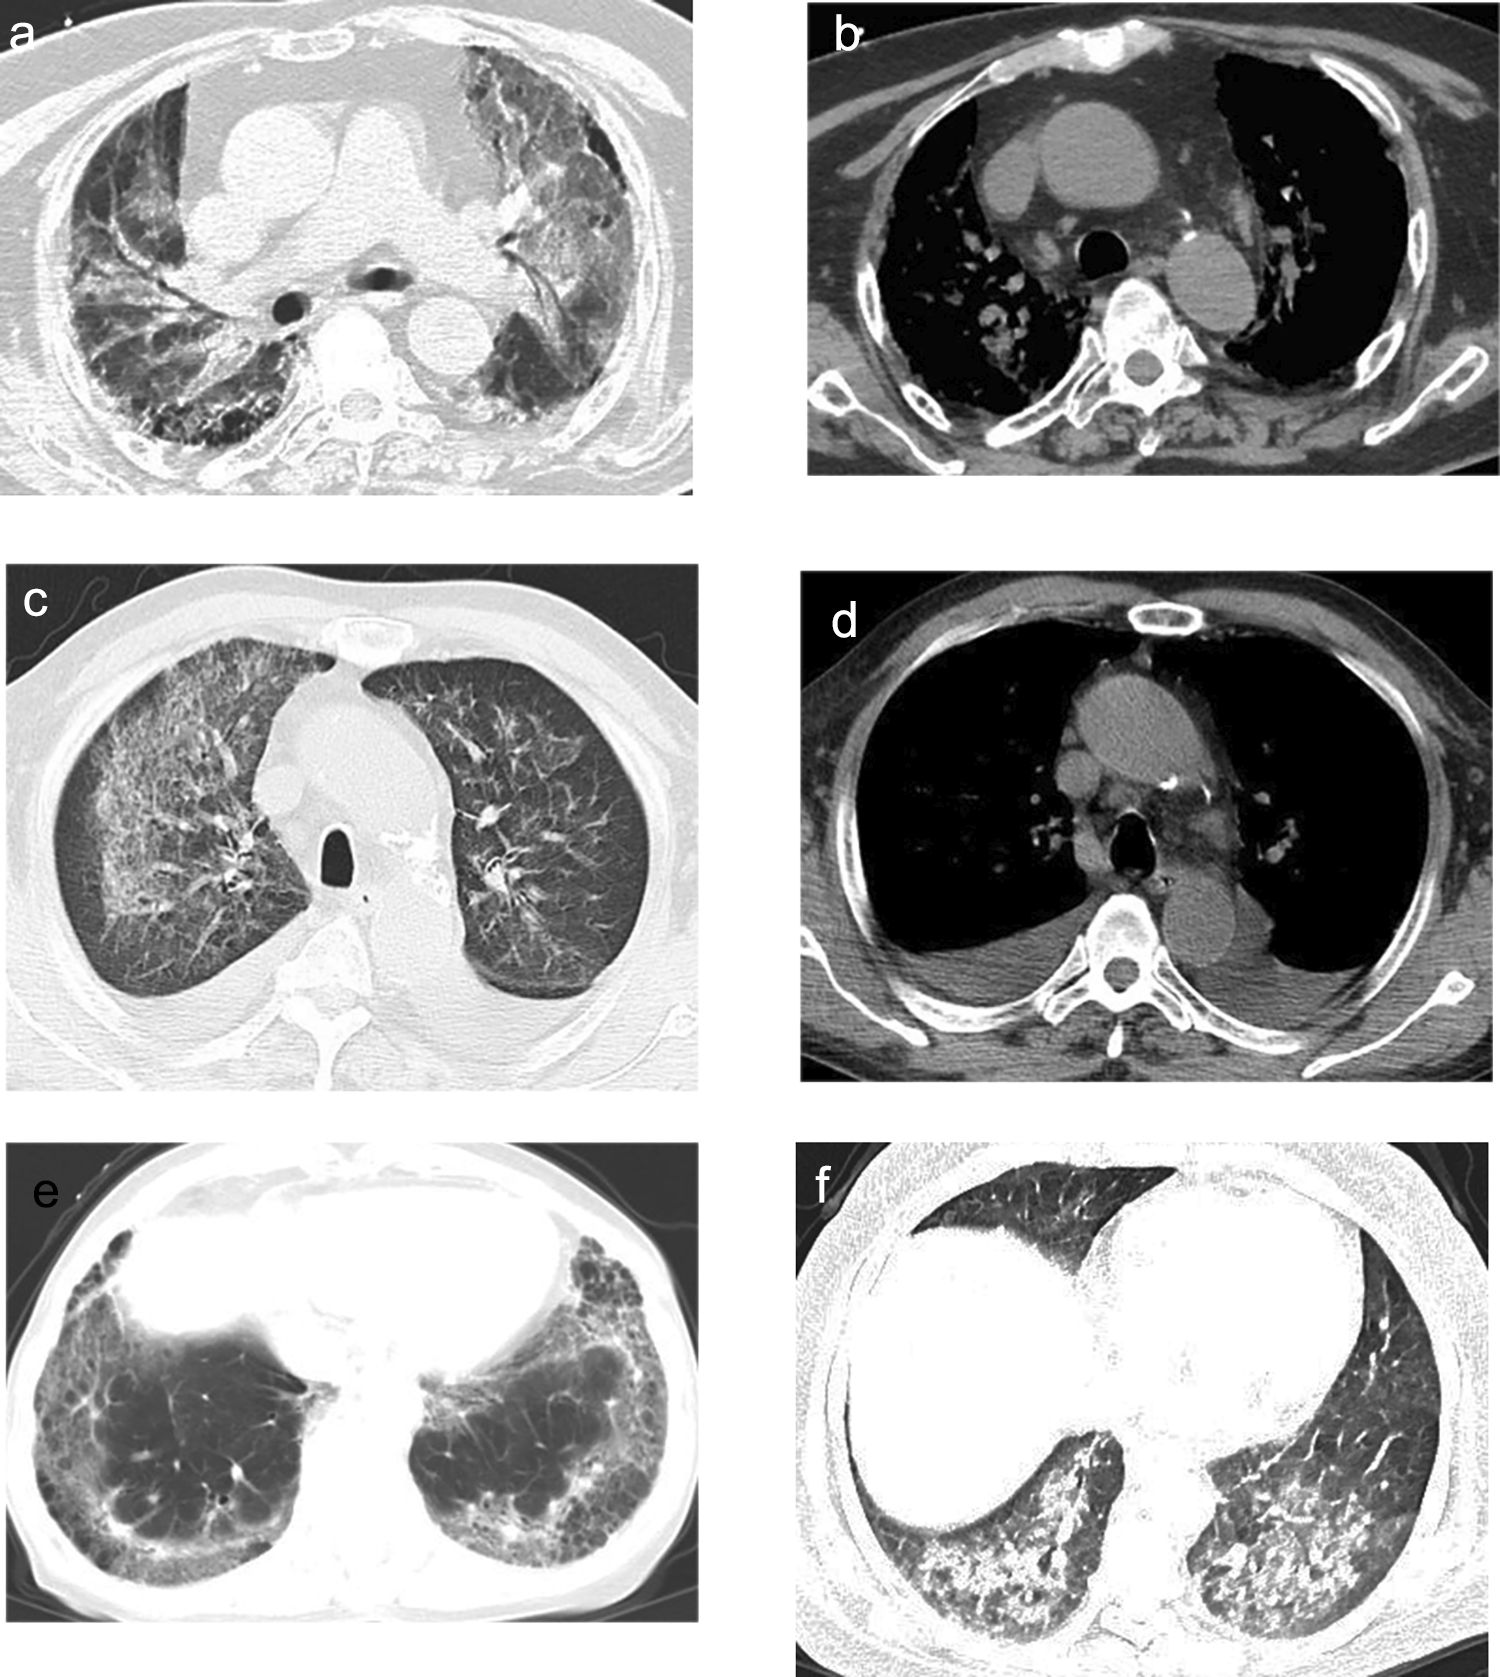

Fig. 3

CT findings of immunocompromised exudative PC. Axial CT images showed bilateral diffuse ground-glass opacities and consolidations (a) with mediastinal lymphadenopathy (b). Bilateral ground-glass reticular opacities (c), pleural effusions, and mediastinal lymphadenopathy (d) were displayed on axial CT. Axial CT image showed bilateral ground-glass reticular opacities with pleural-based involvement (e). Bilateral ground-glass opacities and consolidations were displayed on axial CT (f).